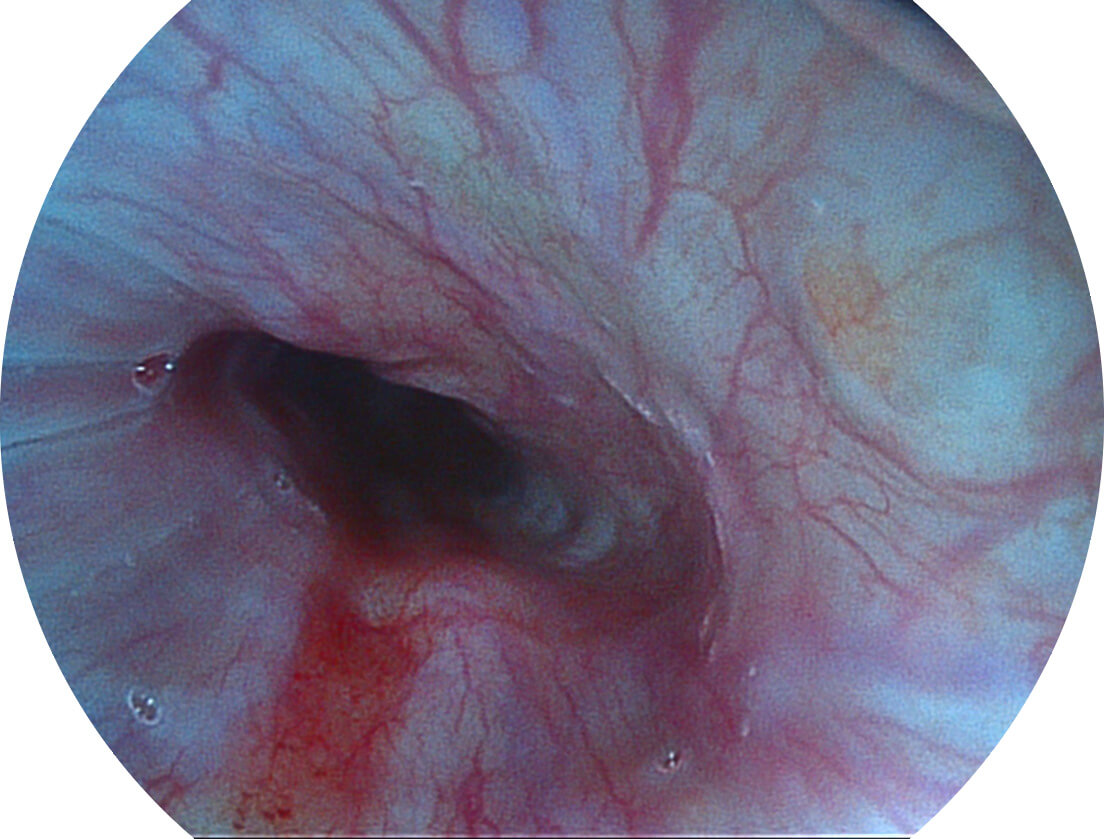

采用光路合束技术,光谱自由度高,实现了更丰富的照明模式,染色模式SFI及VIST,从远景到近景,助力消化道早期疾病诊断。

图像具有高亮度、高黏膜血管颜色对比度的特点,且不改变粘液、食物残渣、粪便的基本颜色,可在中远景下进行观察,助力消化道早期疾病的诊断。

强调浅层黏膜结构的同时,保证照明亮度和提升浅层微血管与中层血管颜色对比度,病变边界更清晰。